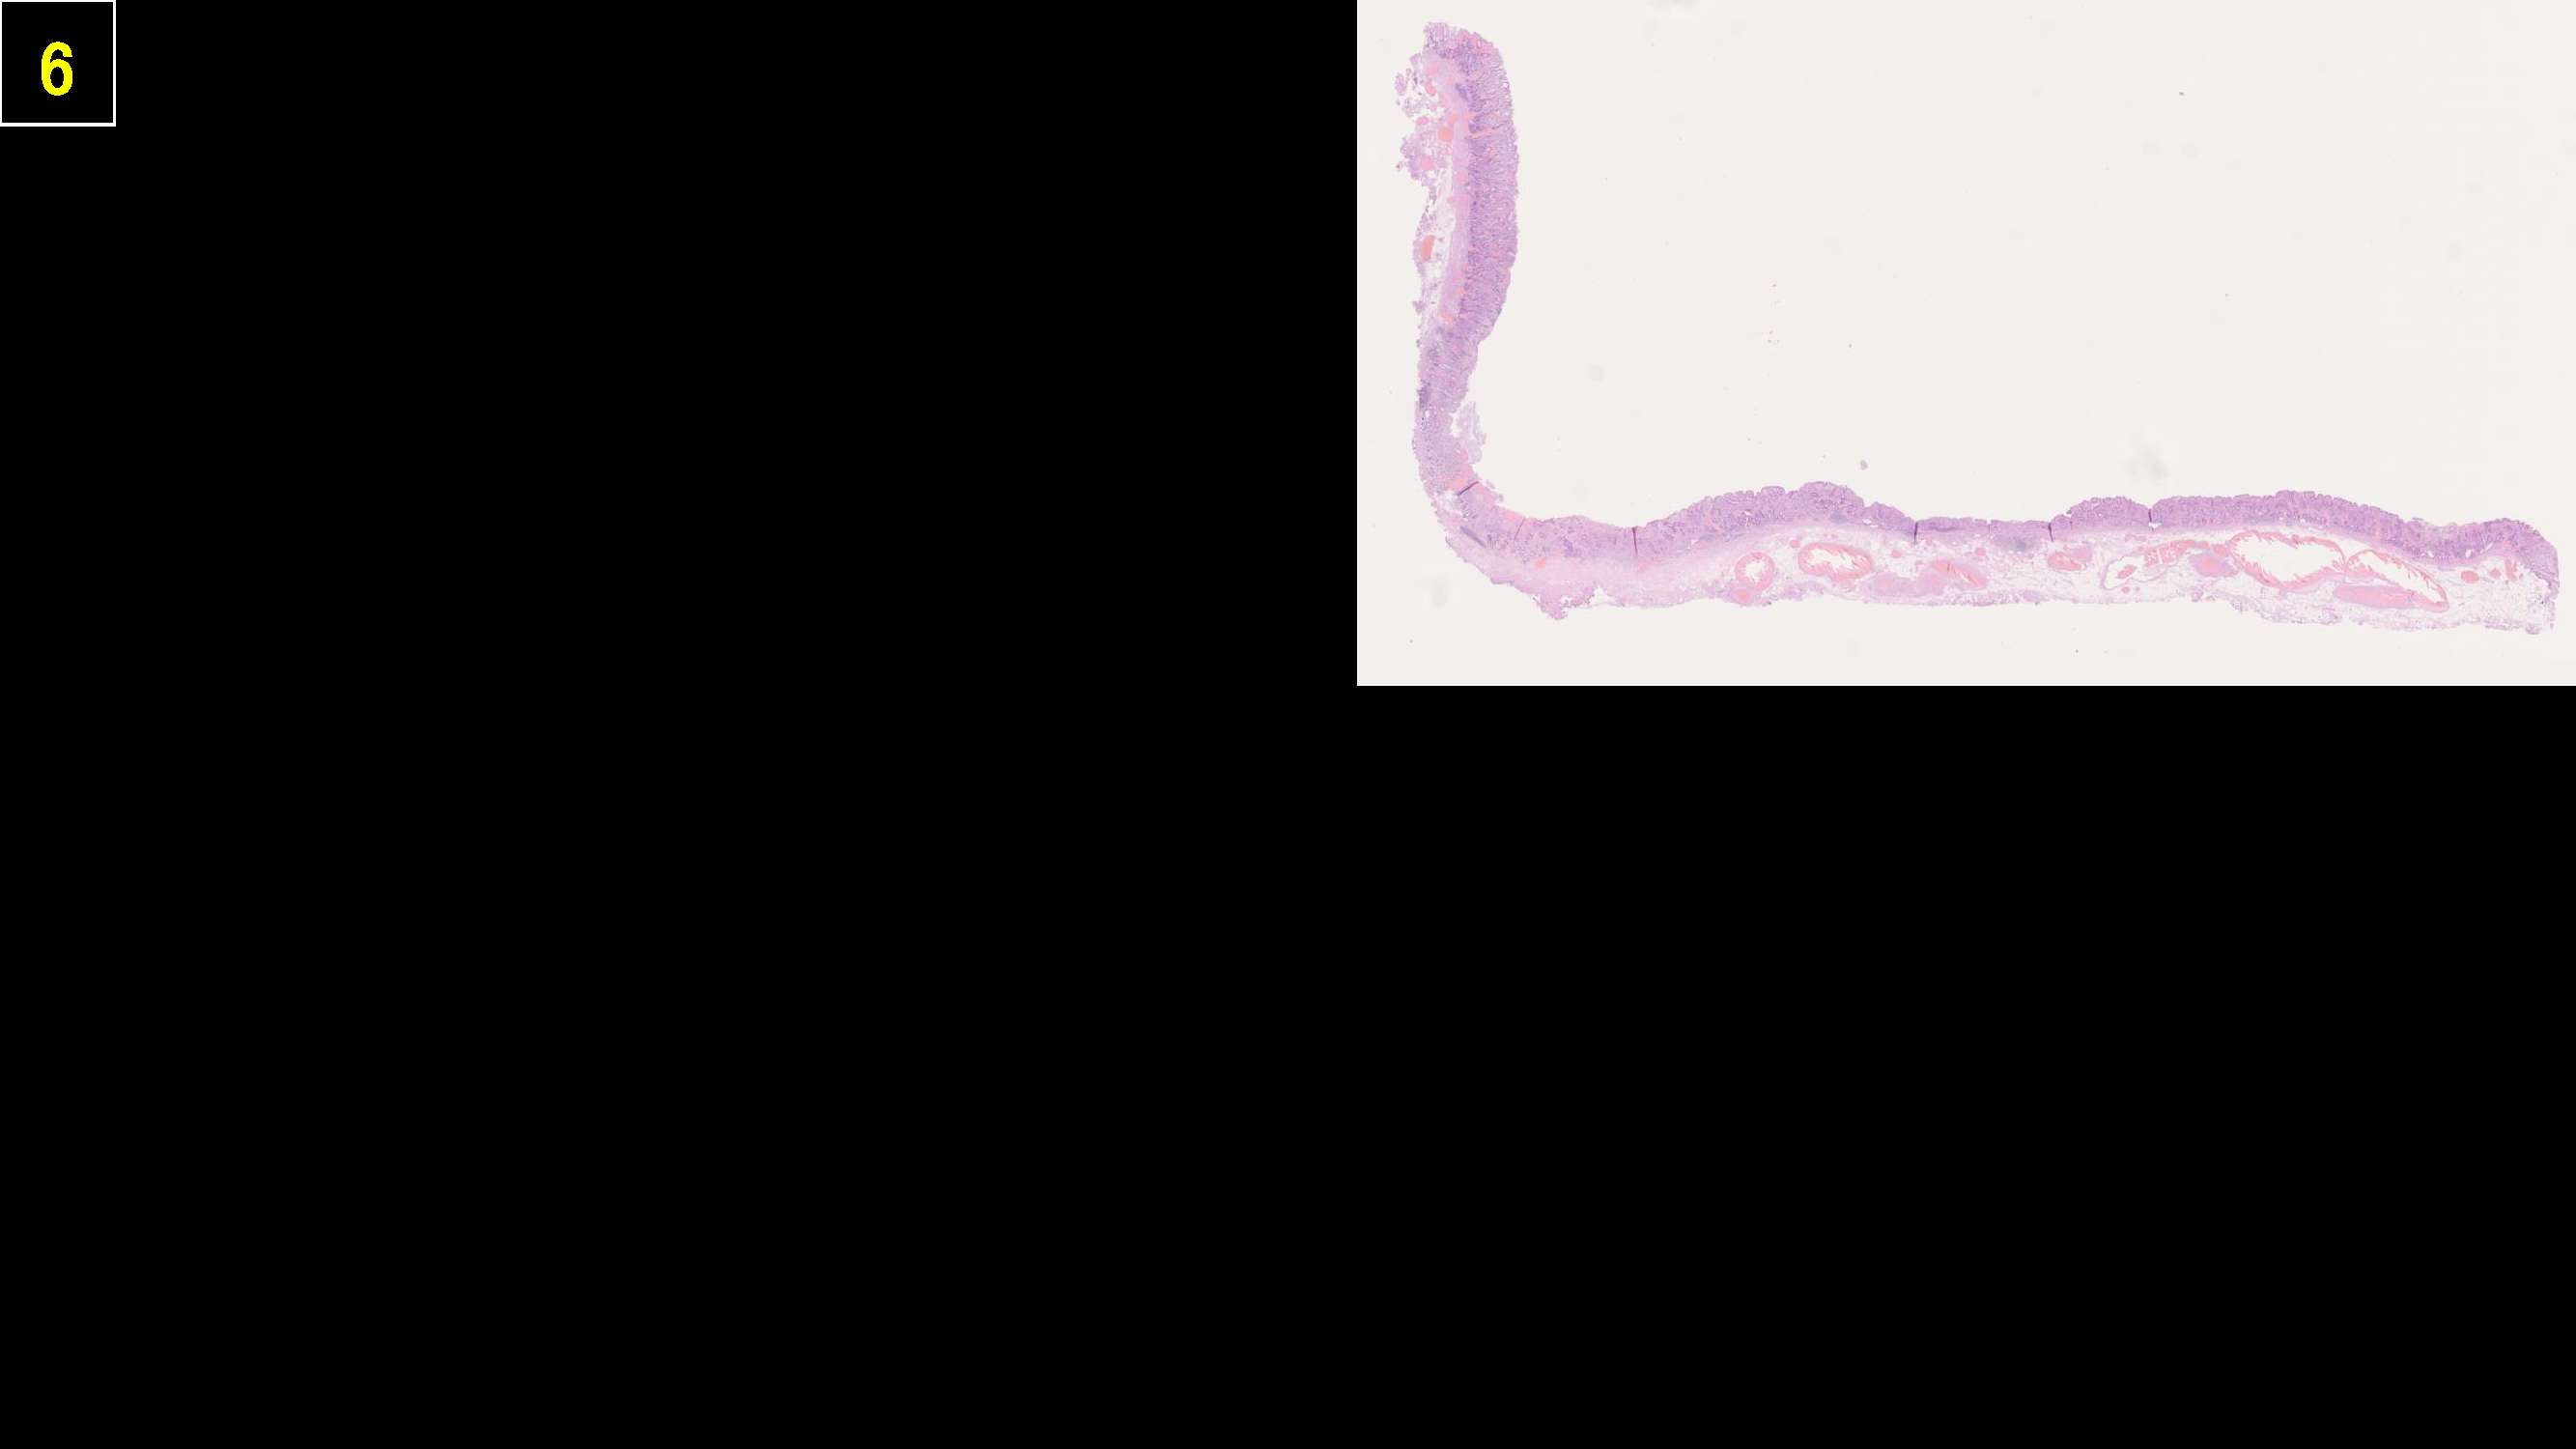

ホーム > 診療科・部門案内 > 消化器センター 消化器内科 > 消化管Mapping > 消化管Mapping~胃~ > 消化管Mapping~胃~ 2025.9.10